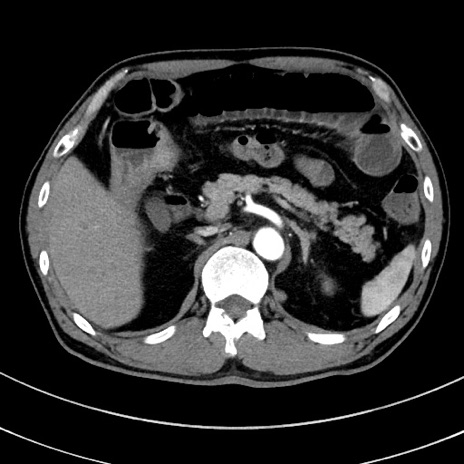

症例8(横断像)

【症例】 60歳代男性

【主訴】 黒色吐物

【現病歴】 4日前から嘔気自覚、2日前の朝食後にも嘔気あり、自分で手で嘔吐反射起こし嘔吐したところ血が混ざっていたため受診。

【既往歴】 5年前汎発性腹膜炎を伴う急性虫垂炎で手術、高血圧、前立腺肥大症、高脂血症

【身体所見】 腹部正中に手術癩痕あり 腹部平坦・軟圧痛なし膨満感あり

【データ】WBC 8400、CRP 4.54